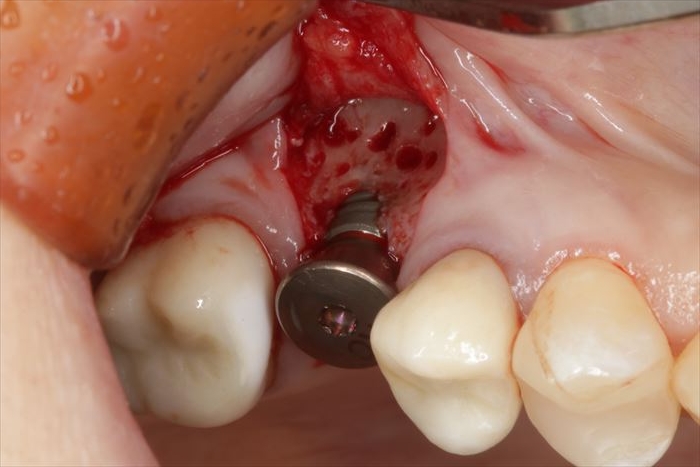

インプラント本体のスクリューホールの保護と歯肉の形態を整えるためにヒーリングキャップを用意します。

ヒーリングキャップを締結しました。

骨増生する部分の皮質骨表面に穴を開けて出血を促します。(デコルチケーション:皮質骨穿孔)

骨増生(骨造成)処置は血液が重要な役割を果たします。出血によって骨芽細胞が送り込まれます。